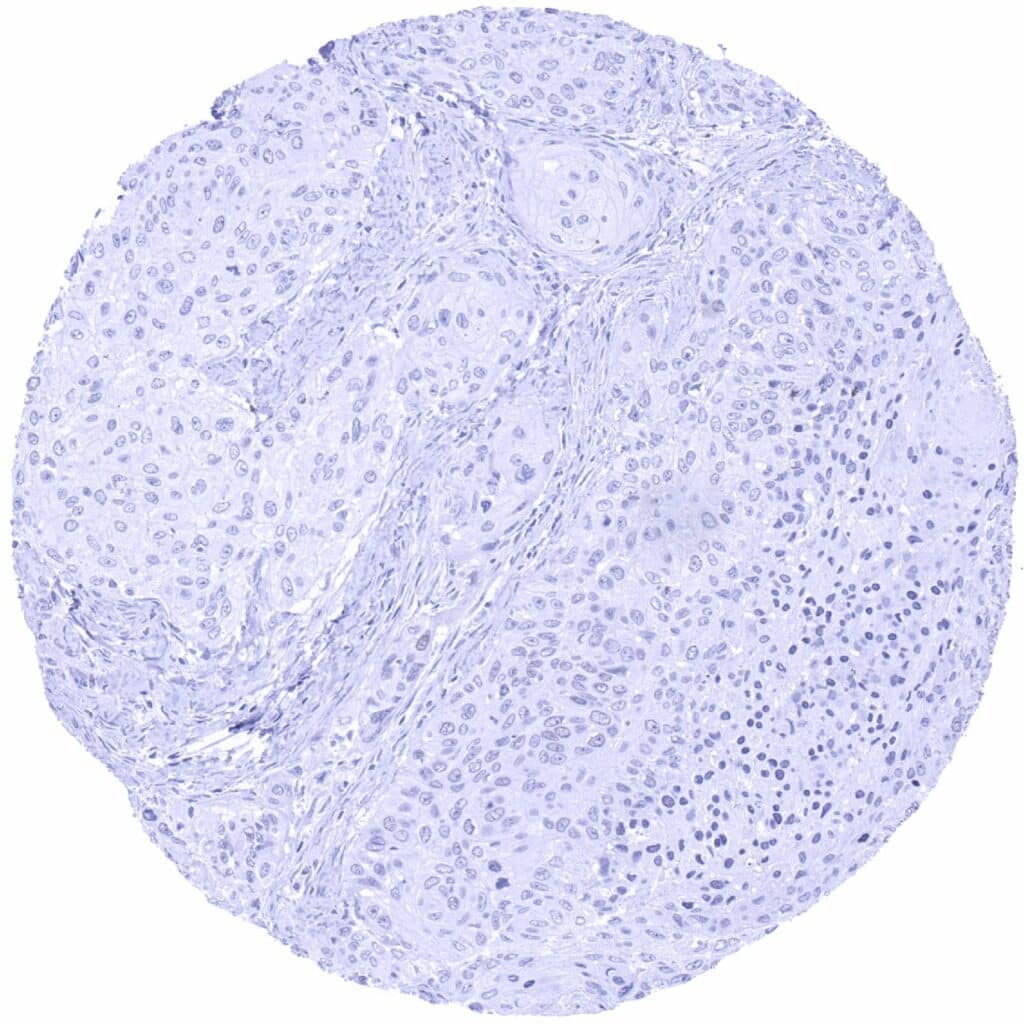

Soft tissue – PAX6 negative leiomyosarcoma